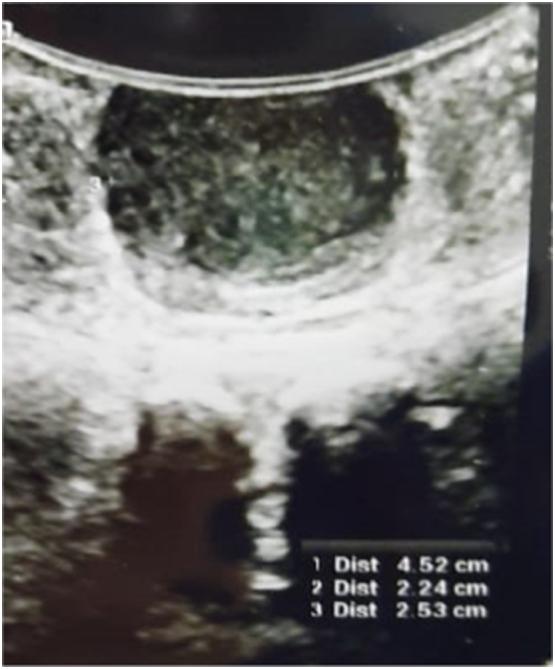

PRESENTATION OF CASE

This article report a case of 31 year old women who complained mass came out from vagina without any urinary symptom and trauma. Physical examination and ultrasound finding suggested that the mass was Gartner Duct cyst. Management in this case was excision of the vaginal cyst. Histopathology examination revealed Deep (aggressive) angiomyxoma.

本文报告一例31岁女性患者,主诉阴道肿物脱出,无任何泌尿系统症状及外伤史。体格检查及超声检查提示肿物为加特纳管囊肿。该病例的治疗方式为切除阴道囊肿。组织病理学检查显示为深部(侵袭性)血管黏液瘤。